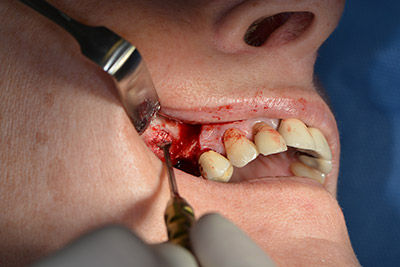

Следващата стъпка е синус лифт с непосредствено имплантиране. Implantmed е предварително настроен на първа позиция за букална фенестрация на стената на максиларния синус.

Фенестрацията е извършена при 35,000 rpm и след това носната лигавица е обработена по посока на челюстта (Фиг. 13 to 14).